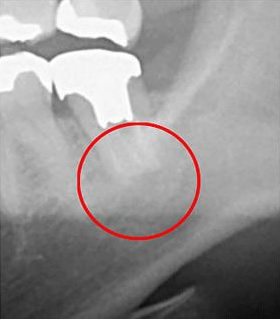

次の写真をご覧ください。同じ部位をCTとレントゲンで撮影したものですが、違いは歴然です。

CT撮影(左)では、暗い領域が確認できます。この部分には、炎症が起きています。しかし、レントゲン写真では異常は見られません。もしレントゲンでしか検査していなかったら、この炎症は見過ごされていました。最悪の場合、抜歯となっていたかもしれません。

当院では、このような事態を回避するため、CTを使用して検査を行います。